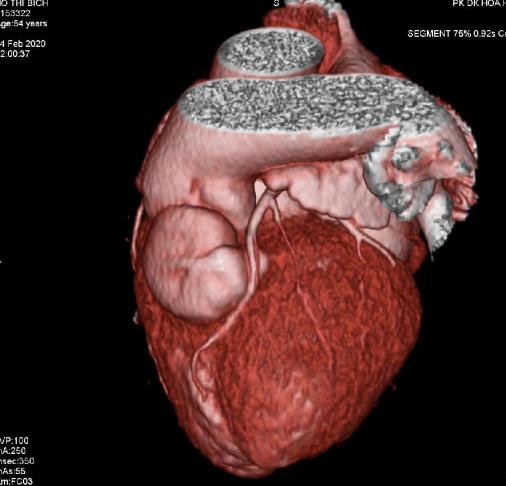

Transthoracic and transesophageal real-time three dimensional echocardiography is a significant advancement in technology. Advances in image processing and display, the addition of three dimensinal imaging capability, and the portability of ultrasound system have increased the availability and utility of TEE to a variety of clinical settings as diagnosis, cardiac catetherization, operation and intensive care.

Currently percutaneous interventions for many structural diseases increase more and more in our country. Interventional cardiologists are now treating a variety of lesions that previously required surgery as mitral stenosis, aortic stenosis, ostium secundum ASD, VSD, PDA, Coronay Fistula…Although Fluoroscopy and 2D TEE are usually used for procedural guidance, real-time three-dimensional TEE offers several important advantages over these modalities.

From October 2010 to May 2020, in MEDIC HCMC, we have already performed 1278 cases of 3DTEE: Mitral stenosis (31%) and other valvulopathie including Mitral Regurgitation, Aortic valvulopathies, Atral Septal Defects (16%) and other shunts as PDA, VSD; then Myxoma and cardiac tumors, Endocarditis, studying prosthetic valves. The other complicated cardiopathies as Coronary artery fistula, Valsalva sinus rupture, Ebstein anomaly.

The percutaneous balloon mitral valvuloplasty, trasncatether closure of ASD and surgery have demonstrated the precised diagnosis of 3DTEE (Figure 1).

Figure 1. Distribution of heart diseases detected by RT-3DTEE